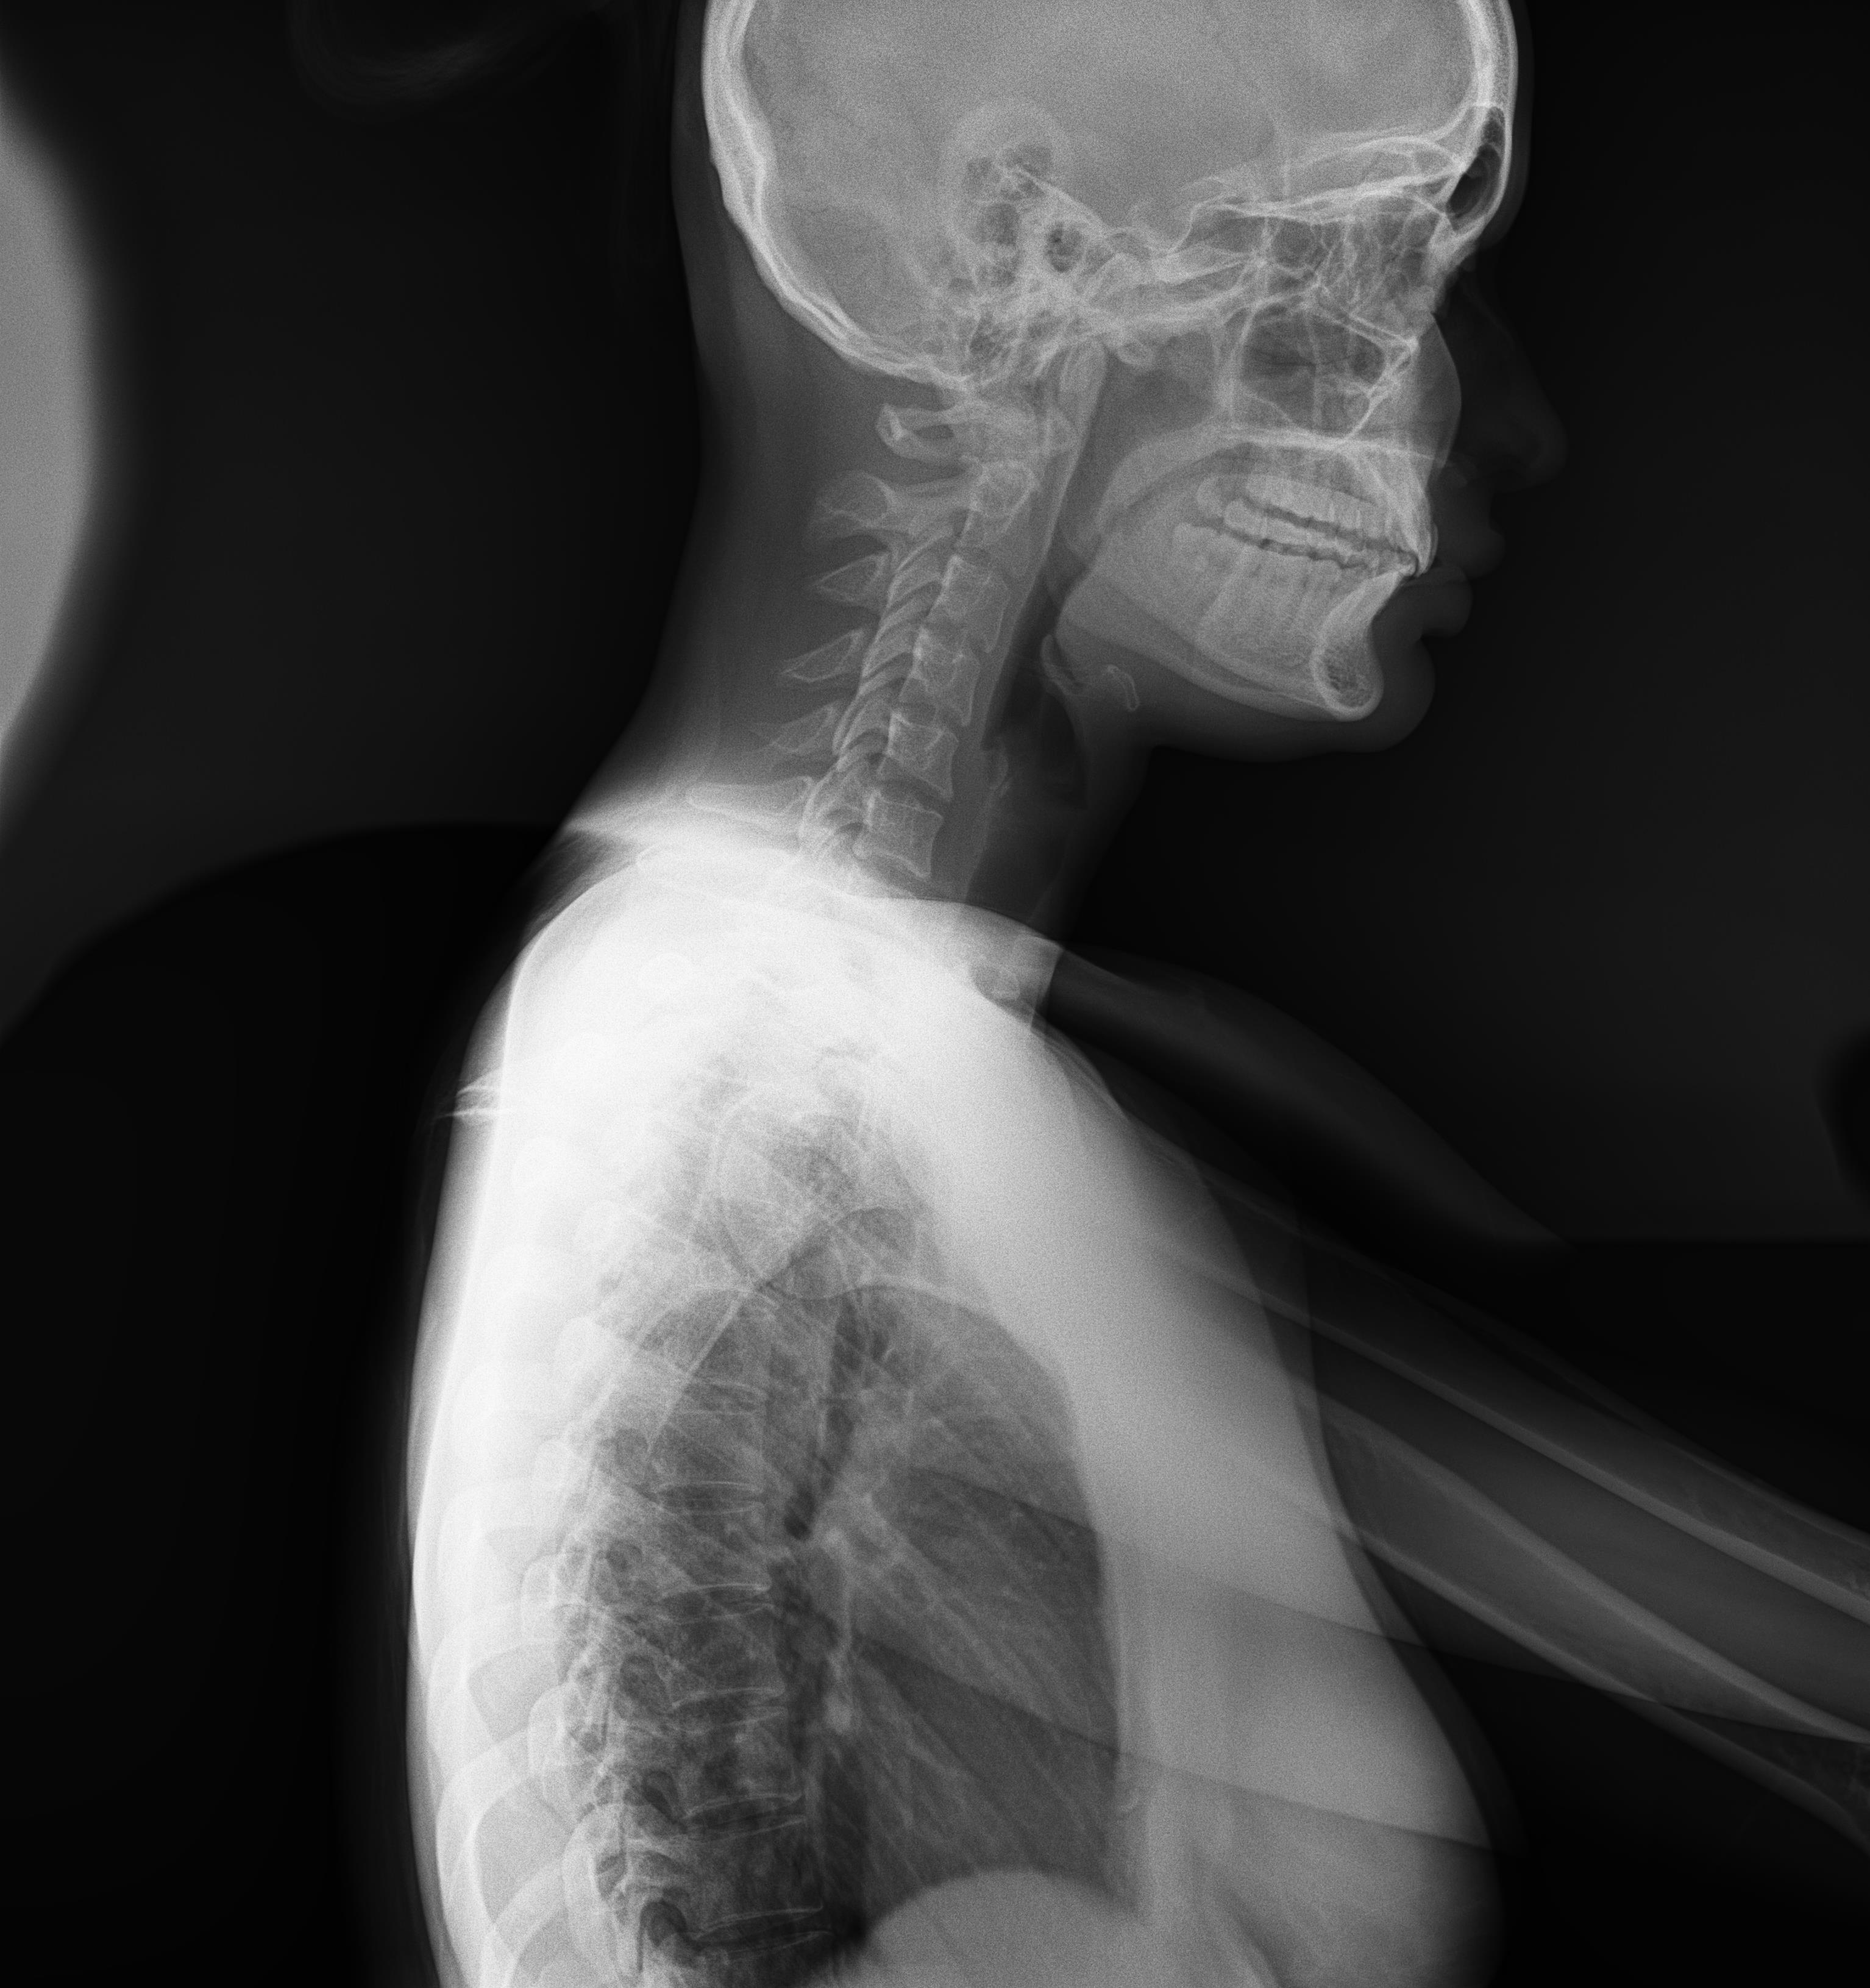

Western Australia, Australia Mar 18, 2021 (Issuewire.com) - Say goodbye to those long waiting times for full spine or leg length studies because within 1 second you can achieve a quick image acquisition with the Longtail – the latest innovative x-ray technology from ATX Medical Solutions. With over 30 years of experience, ATX Solutions has evolved with a profound knowledge of X-ray equipment and its services. The company takes pride in offering a high level of service with unlimited user support to ensure maximum benefits. Recently, a team of experts has initiated the use of this new digital X-ray equipment installed at Capital Radiology in Morley, Western Australia. Clients may ask for the relevance and importance of this newly installed system. Well, to answer their query, Regional Manager at Capital Radiology WA, Joel Scaddan, identified, 3 key features worth mentioning include the following:

- Speed - patients are in and out within 5 minutes so no bookings required;

- Accuracy – no overlapping errors or patient movement compared to other conventional ‘stitched’ systems; and

- Reduced dose compared with stitched systems – due to no overlapping of images and the removal of the anti-scatter grid depending on patient body habitus.

So, what does this all mean? In a nutshell, the Longtail digital radiography system delivers the highest image quality, geometric accuracy whilst reducing the amount of radiation with no image overlap received by the patient per diagnostic study. Moreover, practitioners will find it more convenient as they are now able to deliver swift diagnostic results. Managing Director Roger Davis commented the Longtail will supersede existing technologies for full spine imaging systems that are subject to excessive dose, multiple exposures, and software image adjustment techniques that may compromise the diagnosis.